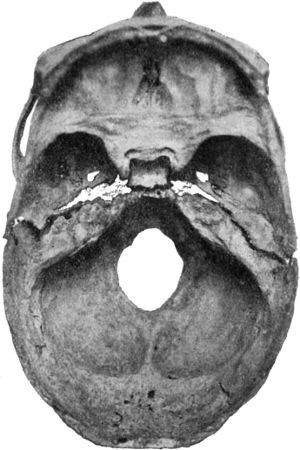

366 191.Transverse Fracture through Middle Fossa of Base of Skull

368 192.Diagram of Extra-Dural Abscess